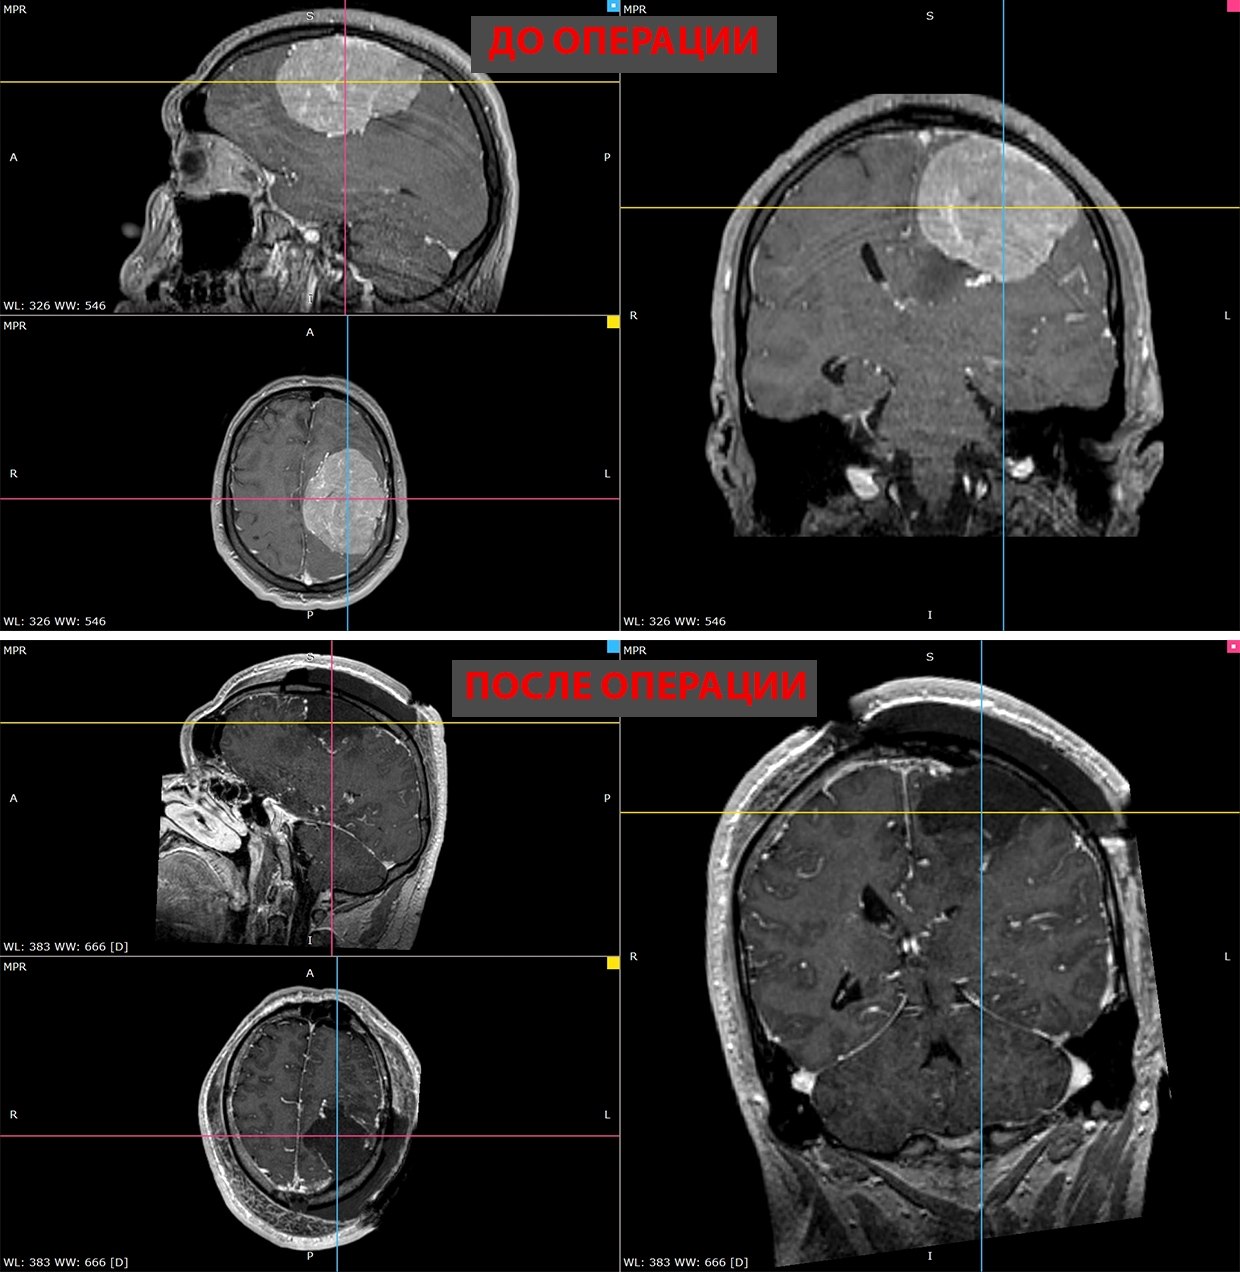

"Ему повсюду отказывали". Новосибирские хирурги удалили пациенту гигантскую опухоль головного мозга

В ноябрепрошлого года у 35-летнего жителя Тюмени начала слабеть правая рука. Вскоре к этому добавились проблемы с речью: формулировать мысли стало трудно. МРТ показало причину — в левом полушарии мозга обнаружили гигантскую менингиому диаметром более 8 см. Опухоль сдавливала речевые центры и двигательные зоны, отвечающие за правую сторону тела. К новому году рука практически отказала, а ходьба стала серьезным испытанием. Однако, когда пациент готовился к плановой операции, диагностика выявила еще одну, смертельную угрозу: тромбоэмболию легочной артерии. Оторвавшийся тромб из вены ноги достиг легких. В такой ситуации риск повторного тромбоза или смертельного кровоизлияния во время операции был запредельным, и ведущие клиники одна за другой стали отказывать мужчине в хирургическом вмешательстве.

В день поступления пациента прооперировали. В течение пяти часов нейрохирурги работали над удалением гигантского новообразования. Врачам удалось сделать невозможное: опухоль была полностью иссечена, при этом удалось избежать повреждения жизненно важных центров и обойтись без кровоизлияний. Результат превзошел ожидания. Уже на следующее утро после вмешательства к пациенту вернулась подвижность в руке. Спустя две недели мужчина самостоятельно ходит, его речь полностью восстановилась, а мучительные эпилептические приступы остались в прошлом.